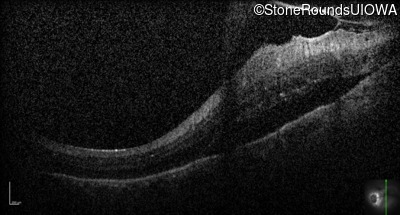

Optical Coherence Tomography - Right - 20/50 +2

Exemplar / OCT Stack

Optical Coherence Tomography - Left - 20/160